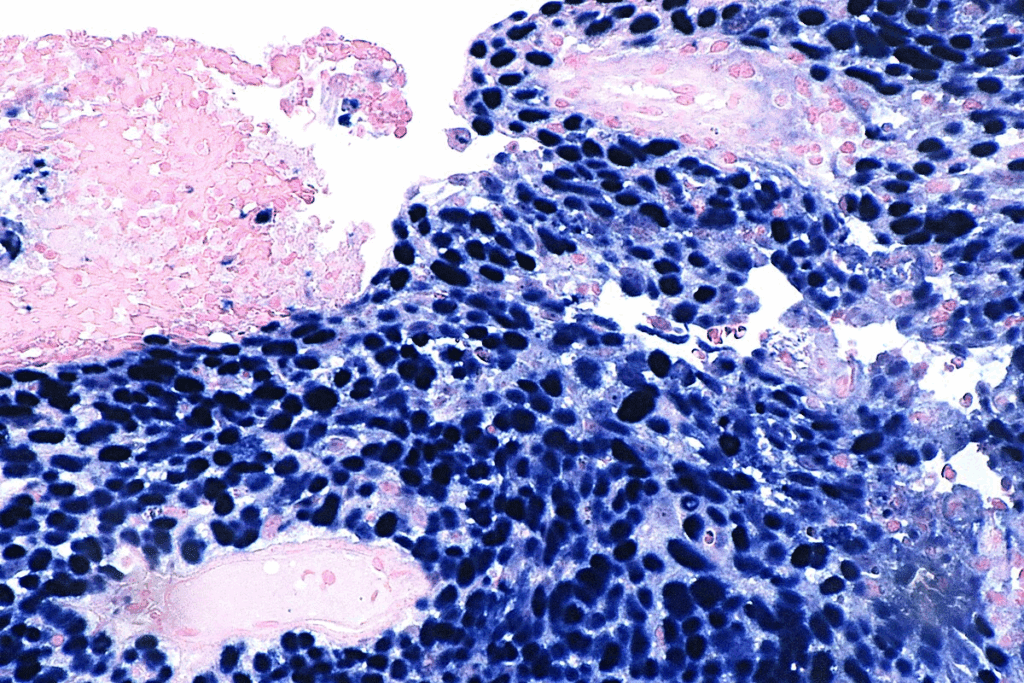

Biopsy and Imaging Tests

If something looks off during the first check, a biopsy is done next. A biopsy takes a tissue sample for cancer cell checks. Tests like X-rays and CT scans help see how far the cancer has spread.

Staging and Grading Explained

After diagnosing oral cancer, the next step is to figure out its stage and grade. Staging looks at the tumor size, if it’s in lymph nodes, and if it’s spread. Grading checks the cancer cells’ look under a microscope, showing how aggressive it is.